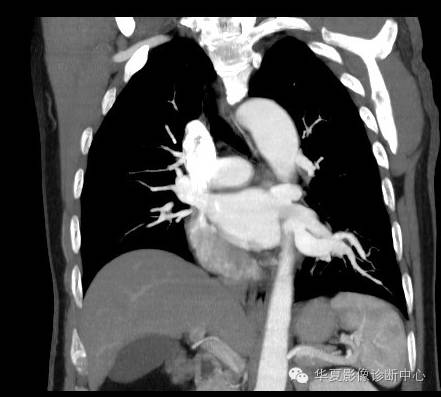

| 病史资料: | 男.51岁。无症状,体检就诊。 |

| 影像表现及分析: | 影像表现:定位左下叶;左下叶体积缩小,整体密度增高,支气管分布正常,其内见血管增多,但是走形正常,未见杂乱、迂曲的血管影;血管连向肺门下方软组织密度结节灶,结节与主动脉分界不清,增强后,见降主动脉发出异常粗大血管供血整个左下叶,左下肺动脉细小。 |

| 确诊依据: | CTA明确左下叶供血动脉为降主动脉发出 |

异常体动脉供应正常下肺基底段完整含义为起源于降主动脉的异常动脉供应下肺基底段,而基底段支气管树和肺实质正常,同时基底段肺动脉缺如或狭窄【大部分缺如(完全型),部分狭窄(不完全型)】;95%以上累及左下肺,因此也称为异常体动脉供应正常左下肺基底段。 病因尚未明确,可能是胚胎发育时期供应肺芽的背主动脉原始小分支退化不全,与肺实质形成异常连接,并影响肺动脉与肺血管床连接而导致此部位肺动脉发育不良,而支气管、肺组织的发育未受影响。本病的病理生理基础为左向左的分流,体动脉供应的肺组织充血,体循环的高压可增加肺血管床的压力和左心负荷,同时也增加肺循环量和压力而增加右心负荷,导致各种临床症群。本病可无临床症状,部分患者可有咯血、呼吸道感染、呼吸困难、充血性心力衰竭。 影像表现:左肺下叶体积缩小,整体密度稍增高,支气管树走形、分布正常,血管增多、稍增粗;增强后显示左下肺动脉幼小,甚至不发育;下叶由主动脉发出的粗大血管供血。 |